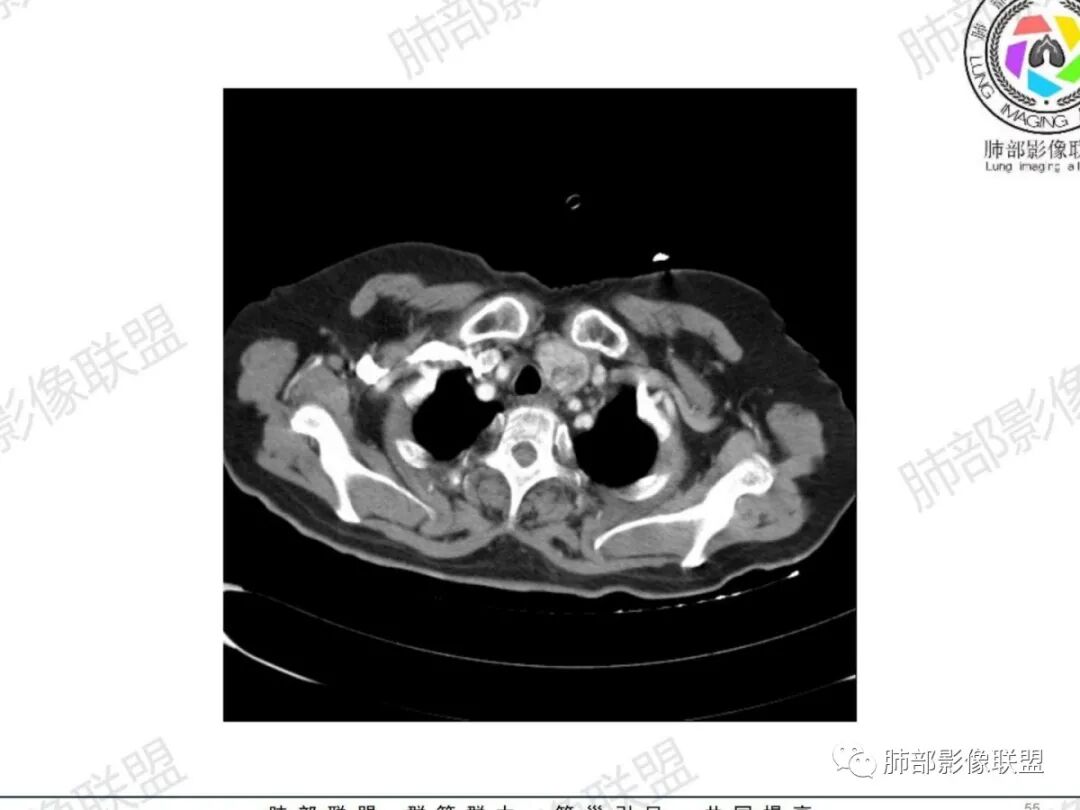

气管右后侧壁结节,结节向气管腔内突出,气管壁增厚,轻度强化,左侧甲状腺占位,考虑气管原发肿瘤,腺样囊性癌?类癌?

女,69反复咳嗽1年,胸闷二天,气管腔内见结节影,病灶突向腔内,管腔狭窄受压呈月牙状改变,增强扫描轻度强化,考虑腺癌?左侧甲状腺病变,不除外转移性病变。

无蒂,无颈,气管侧后壁(特殊部位),虽然是老年女性年龄不符合,但是腺样囊性癌仍做首要考虑,还要考虑鳞癌。

气管右后壁占位,平扫密度稍低于肌肉

内外边缘光滑

宽基底与气管相连